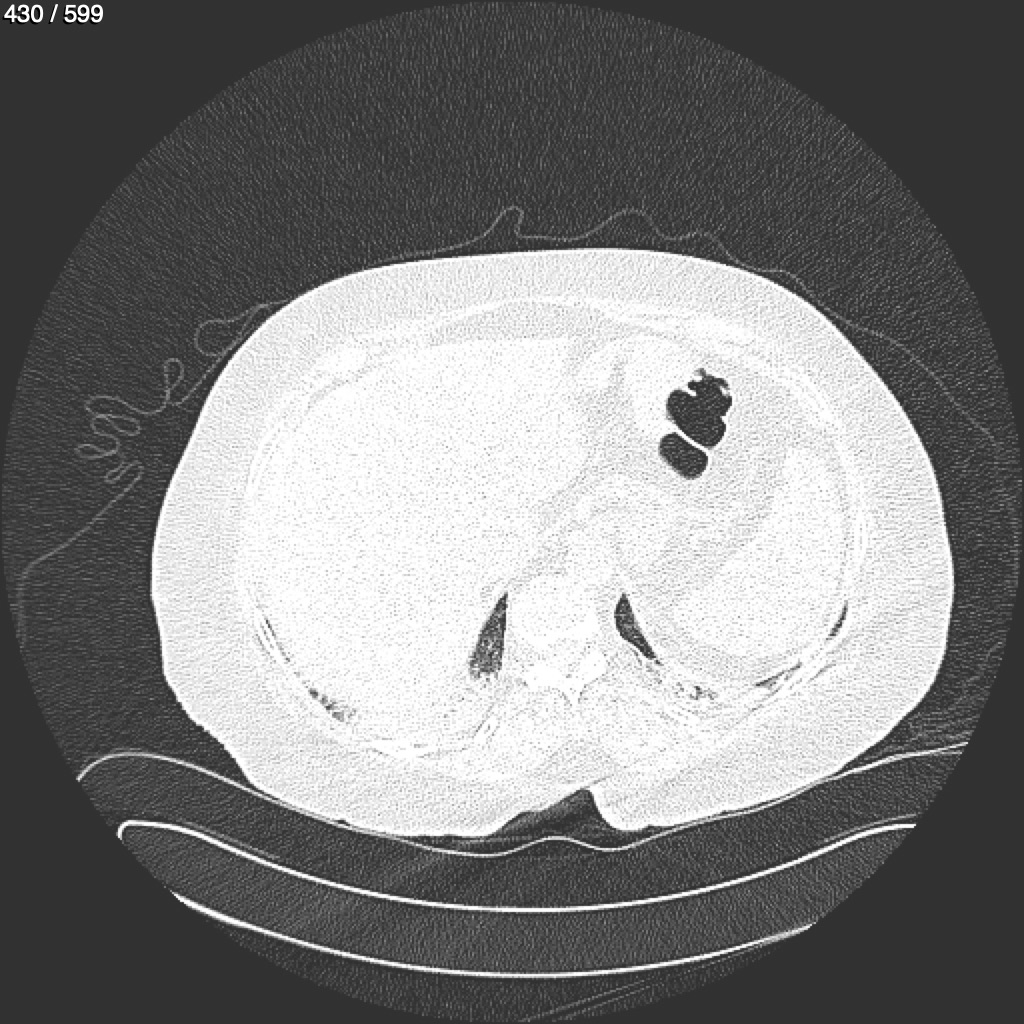

Home G​l​o​r​i​a​ ​G​l​a​d​y​s​ ​B​e​a​s​l​e​y​ ​-​ ​T​ó​r​a​x​ ​T​o​r​a​x​_​S​i​m​p​l​e​ ​(​A​d​u​l​t​o​)